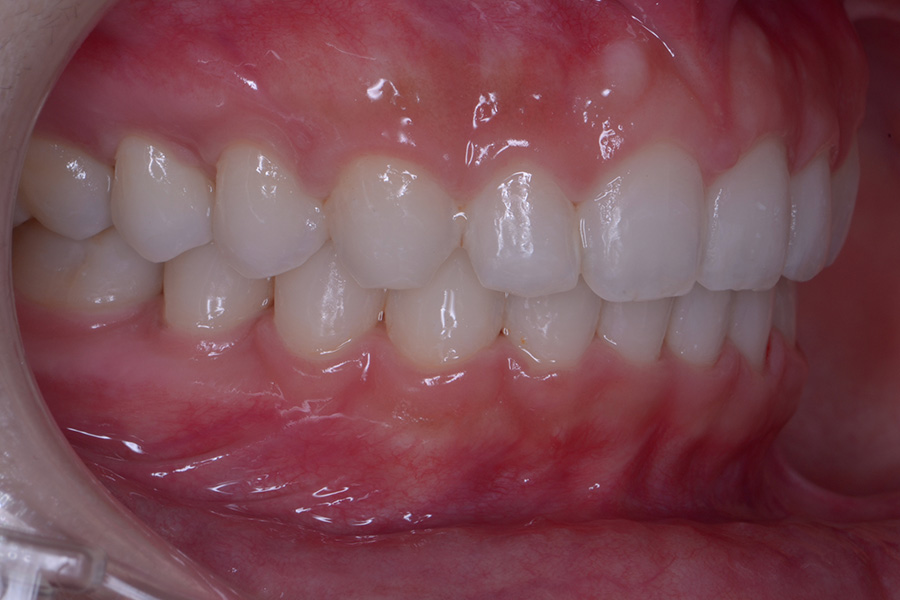

治療前

治療後

主訴 前歯のすきっ歯と捻じれを治したい

治療内容 上下顎ラビアル矯正(表側矯正)